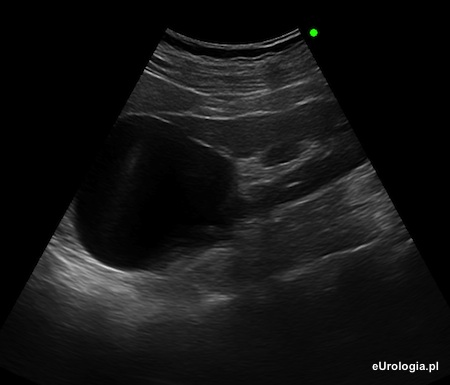

Fot. Obraz USG torbieli prostej nerki lewej.